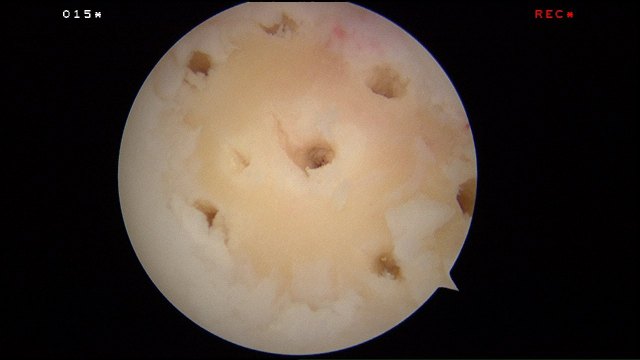

Recent advances have allowed the surgeon to add a scaffold to cover up the cartilage defect after the microfracture has been done to keep the super-clot and the bone marrow cells within the defect.

This allows concentration of the available cells and super-clot to give the best healing potential.

Hyalofast acts as a scaffold for bone marrow aspirate or as a chondroprotective coverage which allows in situ residence of mesenchymal stem cells and other autologus bone marrow elements after their mobilization due to microfracture or perforation procedures. Upon degradation, the HYAFF based scaffold releases natural hyaluronic acid.

The hyalofast scaffold is cut to the right side, mixed with blood and inserted over the cartilage defect arthroscopically.